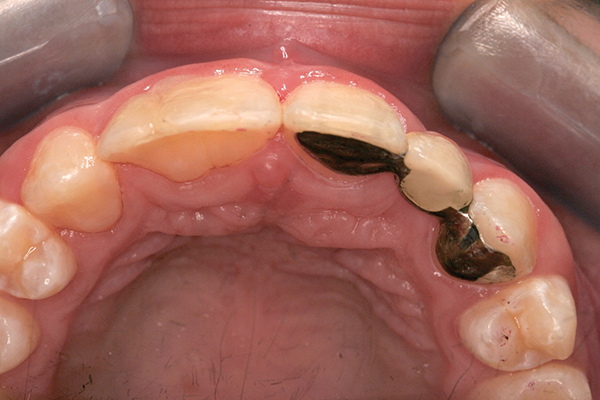

Fig 8. Palatal view.

Figure 8